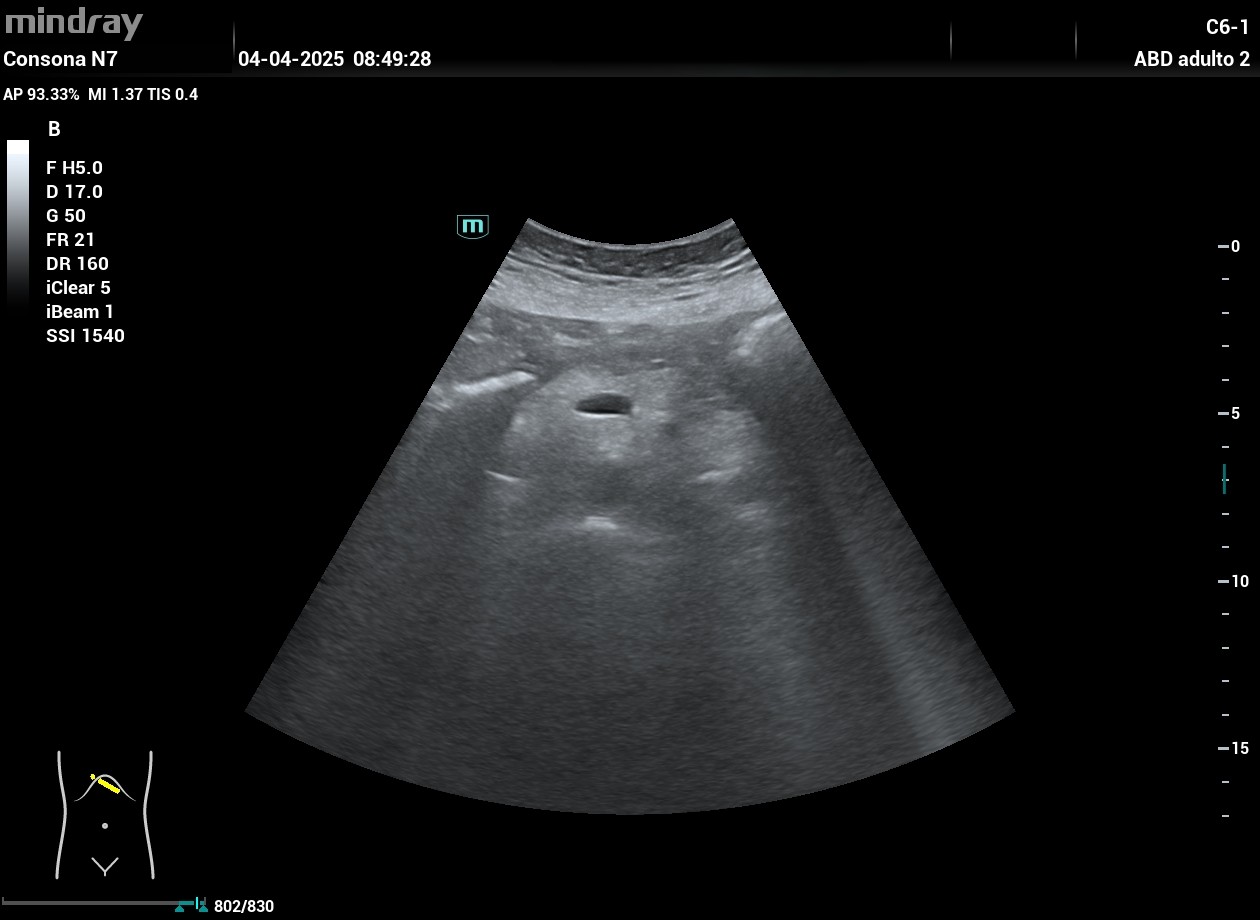

Ecografía hospitalaria: una imagen de contorno pseudonodular y multilobulado con áreas anecoicas de aspecto sólido que condiciona una dilatación del conducto de Wirsung a nivel de la cola pancreática. Se solicita RM con lesión quística multiloculada que impresiona de cistoadenoma seroso.